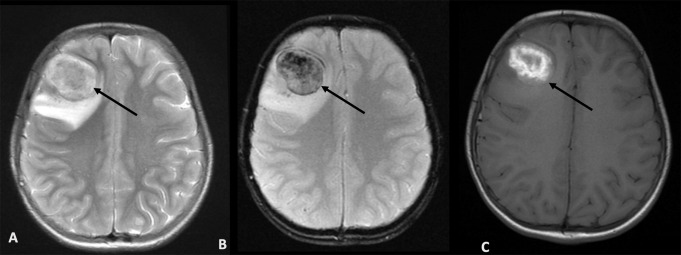

不明原因的神经系统症状可能对先天性免疫错误(IEI)患者的诊断构成挑战,其中病因可能多种多样,不同的病理可能需要不同的治疗方法。脑活检是直接对脑组织进行取样的过程,在历史上提供了组织学和微生物学信息,现在可以用于深层宏基因组下一代分析(mNGS)。我们对2010年至2022年间在英国某三级医疗中心进行脑活检的IEI患儿的临床和诊断数据进行了回顾性分析,其中14例患者符合我们的搜索标准。我们报告了临床特征,不良事件和脑活检的mNGS的额外影响,这些都是进行的。我们发现,在大多数情况下,通过组织或宏基因组学分析,脑活检能够诊断出可控制的并发症(n = 11/14, 79%)。我们发现,mNGS分析提高了29%的IEI病例的脑活检诊断率(n = 4/14)。在71%的病例(n = 10/14)中,脑活检改变了治疗方法。这一系列研究结果为IEI患儿安全且有目的的脑活检提供了强有力的证据。

Unexplained neurological symptoms can pose a diagnostic challenge in patients with inborn errors of immunity (IEI) where the aetiology can be varied, and diverse pathologies may require contrasting treatments. Brain biopsy, the process of sampling brain tissue directly, has historically provided histological and microbiological information and can now be exploited for deep metagenomic next generation analysis (mNGS). We conducted a retrospective analysis of clinical and diagnostic data on paediatric patients with IEI who had a brain biopsy between 2010 and 2022 at a UK tertiary centre where 14 patients fulfilled our search criteria. We report on clinical characteristics, adverse events and the additional impact of mNGS of brain biopsies, where these were conducted. We found that brain biopsy enabled diagnostics with manageable complications in most cases, either by tissue or metagenomics analysis (n = 11/14, 79%). We found that mNGS analysis improved the diagnostic yield of brain biopsy in 29% of IEI cases (n = 4/14). Brain biopsy enabled a change in management in 71% of cases (n = 10/14). This series provides compelling evidence for the safe and purposeful use of brain biopsy in children with IEI.